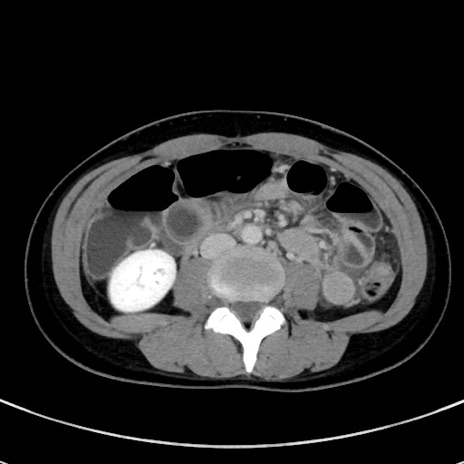

冠状断像

【症例】20歳代女性

【主訴】嘔吐、下腹部痛

【現病歴】昨日夕食後に嘔吐し下腹部痛が出現。本日になっても嘔吐持続し改善しないため来院。

【身体所見】意識清明、BT 37.2℃、BP 108/67mmHg、腹部:平坦、やや硬、下腹部正中から右にかけて圧痛あり、反跳痛軽度あり、tapping pain(+)。

【データ】WBC 13600、CRP 14.94